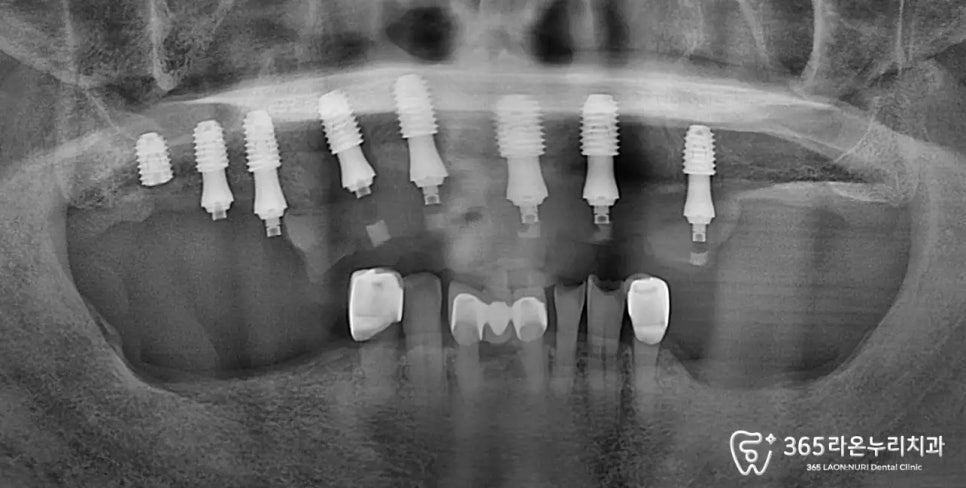

디지털 엑스레이를 자세하게

확인해보면

오랜 틀니 생활로 흡수된

치조골들을 확인할 수 있는데요.

임플란트는 인공치근(픽스처)이

골 유착을 하여 뼈에서부터

지탱하는 건데요.

만약 건강한 뼈가 없다면

당연히 임플란트 식립이 불가능합니다.

끝으로 엑스레이를 찍어

보철까지 잘 들어갔는지

확인 후 진료를 마무리 하게 됩니다.